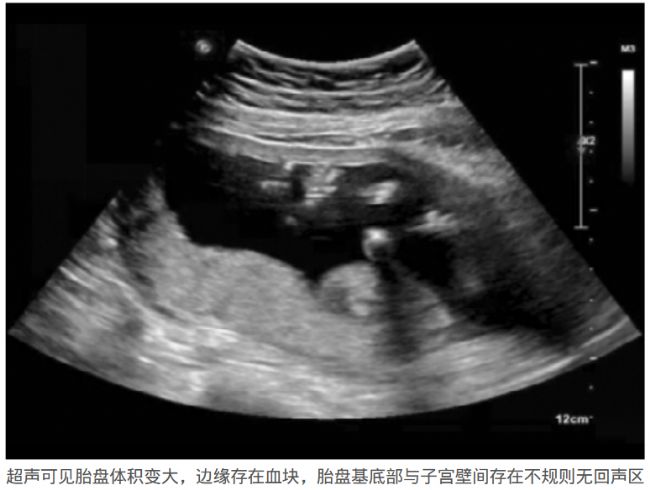

在胎盤早剝的超聲影像中,可見(jiàn)胎盤出現(xiàn)了異常增厚,體積變大,邊緣出現(xiàn)凝血塊,且顯示異常血腫部分無(wú)血流信號(hào)。MRI影像在輔助胎盤早剝的診斷中,可以通過(guò)觀察胎盤后方有無(wú)血腫形成,胎盤后間隙及鄰近胎盤、鄰近子宮肌層有無(wú)增厚,T2信號(hào)是否降低來(lái)診斷胎盤早剝,為臨床診斷提供重要依據(jù)。